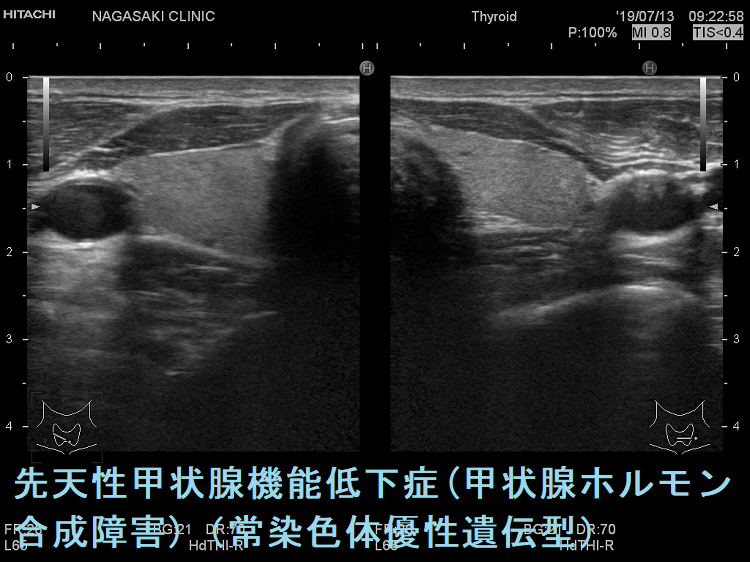

ケース②

遺伝性甲状腺ホルモン合成障害で、サイログロブリン異常症(サイログロブリン遺伝子異常症)以外は、血中サイログロブリンが上昇するにも関わらず、甲状腺自体の破壊性変化に乏しく、マシュマロ様の軟らかい腺腫様甲状腺腫の形態を取る事があります。

遺伝性甲状腺ホルモン合成障害の超音波(エコー)画像は色々なパターンがあります。

- 常染色体優性遺伝型;腺腫様甲状腺腫の形態になります。